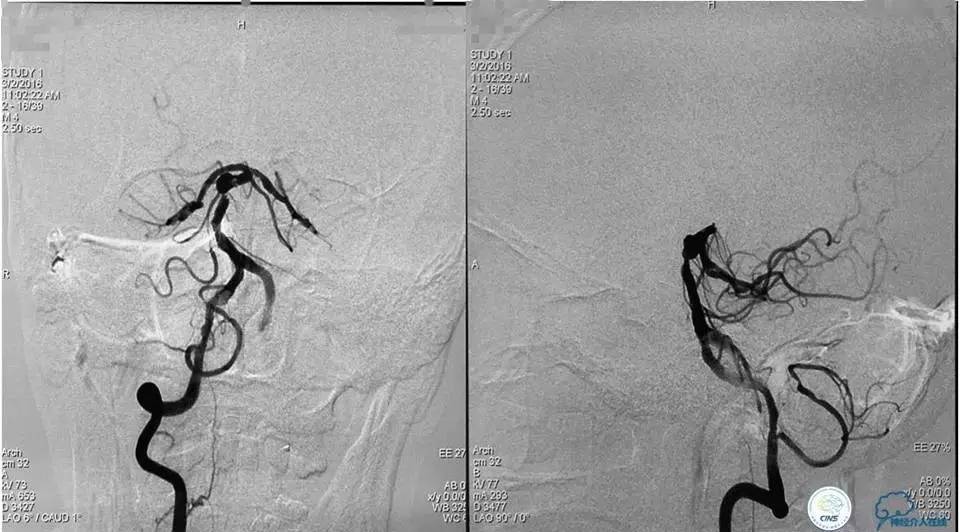

(2)支架结合弹簧圈栓塞动脉瘤

将Traxcess14引导Headway17准备送入下干,微导丝能够顺利进入下干,但微导管无法跟进,被LVIS JR支架网丝卡住,此时发现支架变形,呈灯笼状完全覆盖下干。

工作位造影

Traxess14微导丝携带Echelon10直头微导管穿过LVIS JR支架网孔进入瘤腔内,送入弹簧圈数枚并解脱,直至造影显示动脉瘤完全栓塞,解脱左后1枚弹簧圈。行工作位及标准正侧位造影。